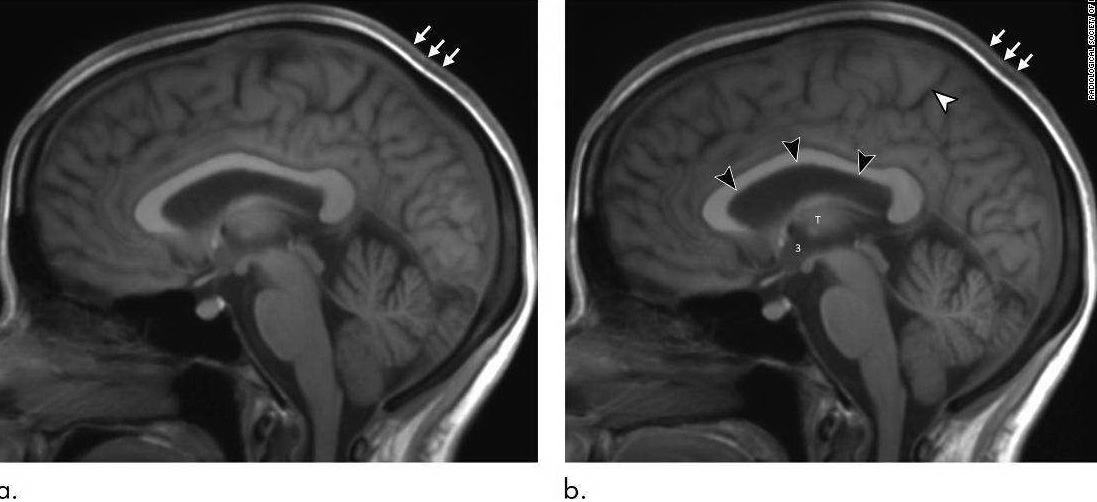

أمثلة على التغيرات في الغدد النخامية لرواد الفضاء بعد رحلتهم الفضائية.

أظهرت الغدة النخامية في ستة من رواد الفضاء في الدراسة أيضًا علامات تشوه ، على الأرجح استجابة للضغط داخل الجمجمة.

وقال الدكتور كرامر "وجدنا أن الغدة النخامية تفقد ارتفاعها وهي أصغر بعد الرحلة مما كانت عليه قبل الرحلة". "بالإضافة إلى ذلك ، فإن قبة الغدة النخامية هي في الغالب محدبة في رواد الفضاء دون التعرض المسبق للجاذبية الصغرى ولكنها أظهرت أدلة على التسطيح أو التقلب بعد الطيران. هذا النوع من التشوه يتوافق مع التعرض للضغوط داخل الجمجمة المرتفعة."